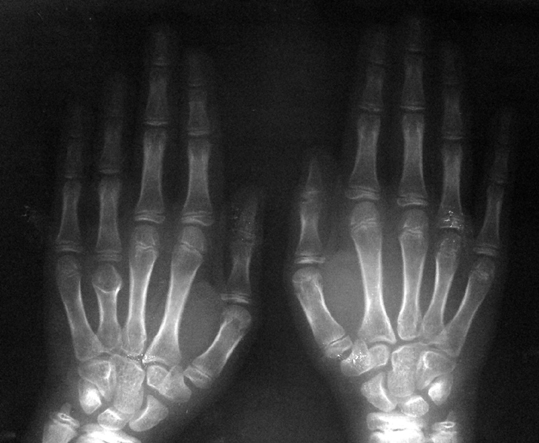

El parmağı (metakarp) ve ayak parmağı (metatars) kısalıkları doğuştan tek başına, geniş bir sendrom grubuyla birlikte, travma sonrası, Freiberg hastalığı (avasküler nekroz) sonrası görülebilir.

Doğuştan metakarp ve metatars kısalığının görülme sıklığı 1/1000’den azdır. Kadınlarda erkeklere göre 5 kat daha fazla görülür ve sıklıkla (%72) iki taraflıdır. En sık 4. parmak tutulur. Bu tür olgularda sorunun nedeni tam olarak bilinmemekle brlikte deformitenin genellikle epifiz plağının erken kapanmasından kaynaklandığı düşünülmektedir.

Metakarp kısalığında kozmetik görünümün bozulması ve dominant elin kullanımı sırasında yorulma, metatars kısalığında ise kozmetik haricinde metatarsalji, kısa parmağın dorsale kayması sonucu deformite oluşması, plantar yönde açılanması sonucu ağrı ve bası ülserleri, ve ayakkabı giymede zorluk nedeniyle ameliyat gerekebilir.

Doğuştan metakarp ve metatars kısalıklarının redavisi için pek çok teknik tanımlanmakla birlikte en çok akut uzatma sonrası kemik uçlarına greft konması ve distraksiyon osteogenezi (kallotasis) kullanılmaktadır. 1 cm.den daha fazla uzatma gereken olgularda kallotasis yöntemi önerilmektedir. Kliniğimizde de metatars ve metakarp uzatma için unilateral eksternal fiksatör ve sirküler eksternal fiksatör yardımıyla distraksiyon osteogenezi yöntemi tercih edilmektedir.